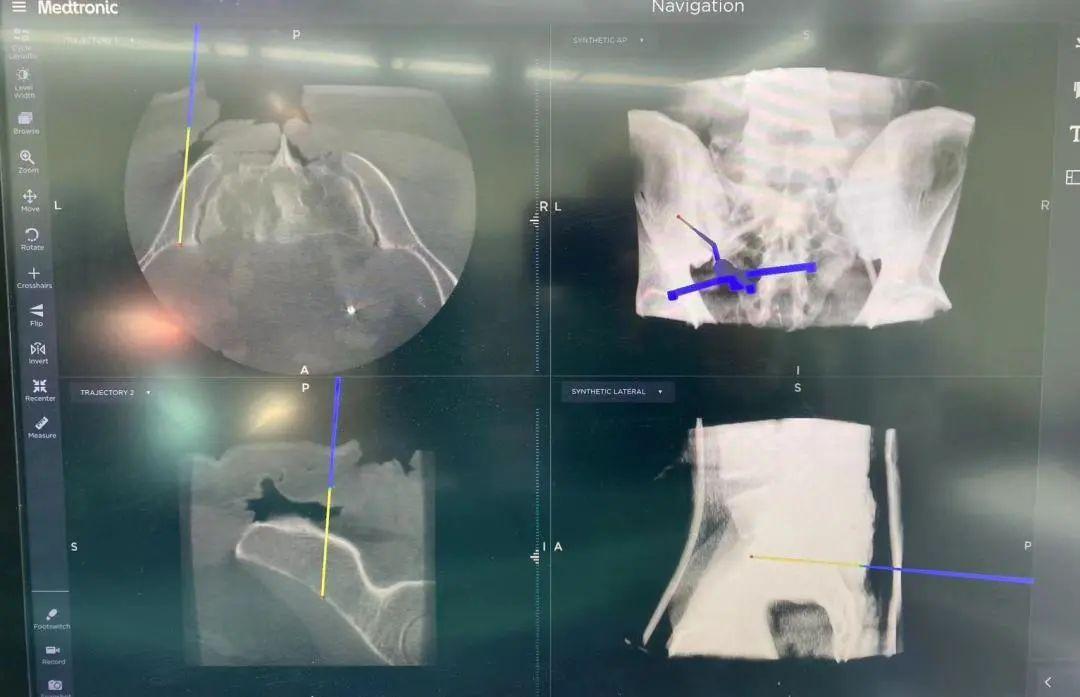

“O”型臂導(dǎo)航系統(tǒng)是一種先進(jìn)的骨科手術(shù)輔助設(shè)備,能精準(zhǔn)定位腫瘤。該系統(tǒng)由“O”型臂術(shù)中影像和手術(shù)導(dǎo)航系統(tǒng)組成,在骨科手術(shù)中發(fā)揮著重要作用,為手術(shù)醫(yī)生實(shí)時(shí)提供術(shù)中三維立體影像,使得手術(shù)醫(yī)生的視角更廣,幫助醫(yī)生避開(kāi)周圍重要的血管和神經(jīng),精準(zhǔn)定位病變部位和范圍,確保了腫瘤的完整切除和正常骨質(zhì)的最大程度保留,大大提高了手術(shù)的安全性。

精準(zhǔn)切除腫瘤后,借助骨腫瘤科自主研發(fā)的3D打印組合式半側(cè)骶骨假體進(jìn)行重建。并在O臂導(dǎo)航系統(tǒng)的引導(dǎo)下,精確放置假體和螺釘,進(jìn)一步提升患者的重建效果。此外,該系統(tǒng)還可以縮短手術(shù)時(shí)間,加快患者的康復(fù)。